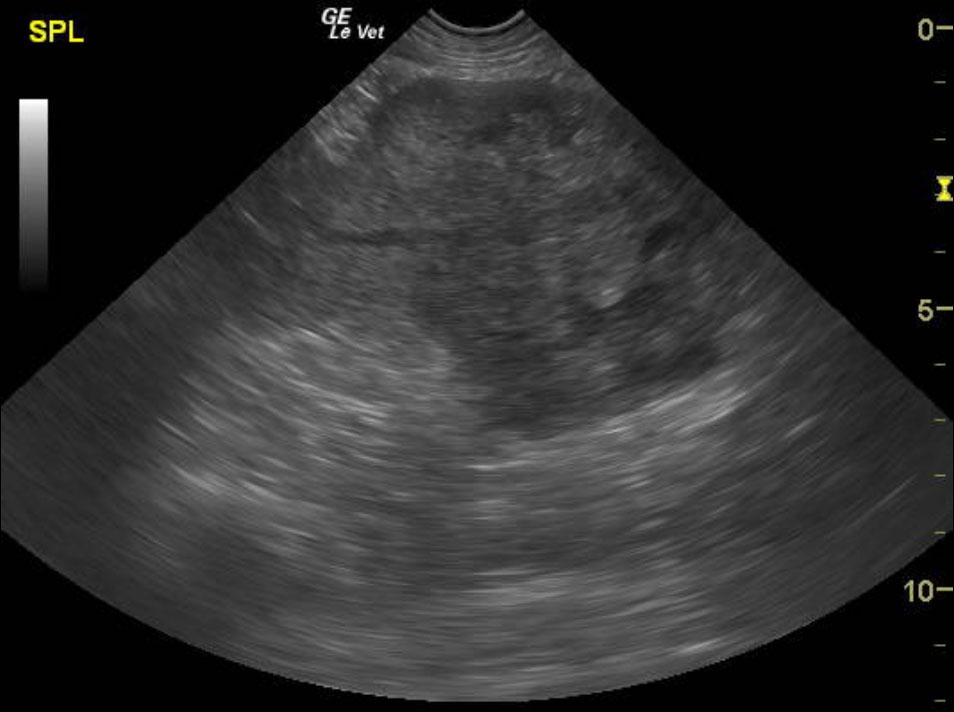

An 11 year old, MN, Rhodesian Ridgeback dog was presented for nonspecific symptoms (ADR). Abdominal mass was palpated. The dog had a subnormal temp (98.8) and pale mucus membranes. Altered CBC/Chem/UA values included leukocytosis, mild azotemia, and mild hypoglobulinemia. Radiographs demonstrated a mass effect in the right abdomen.